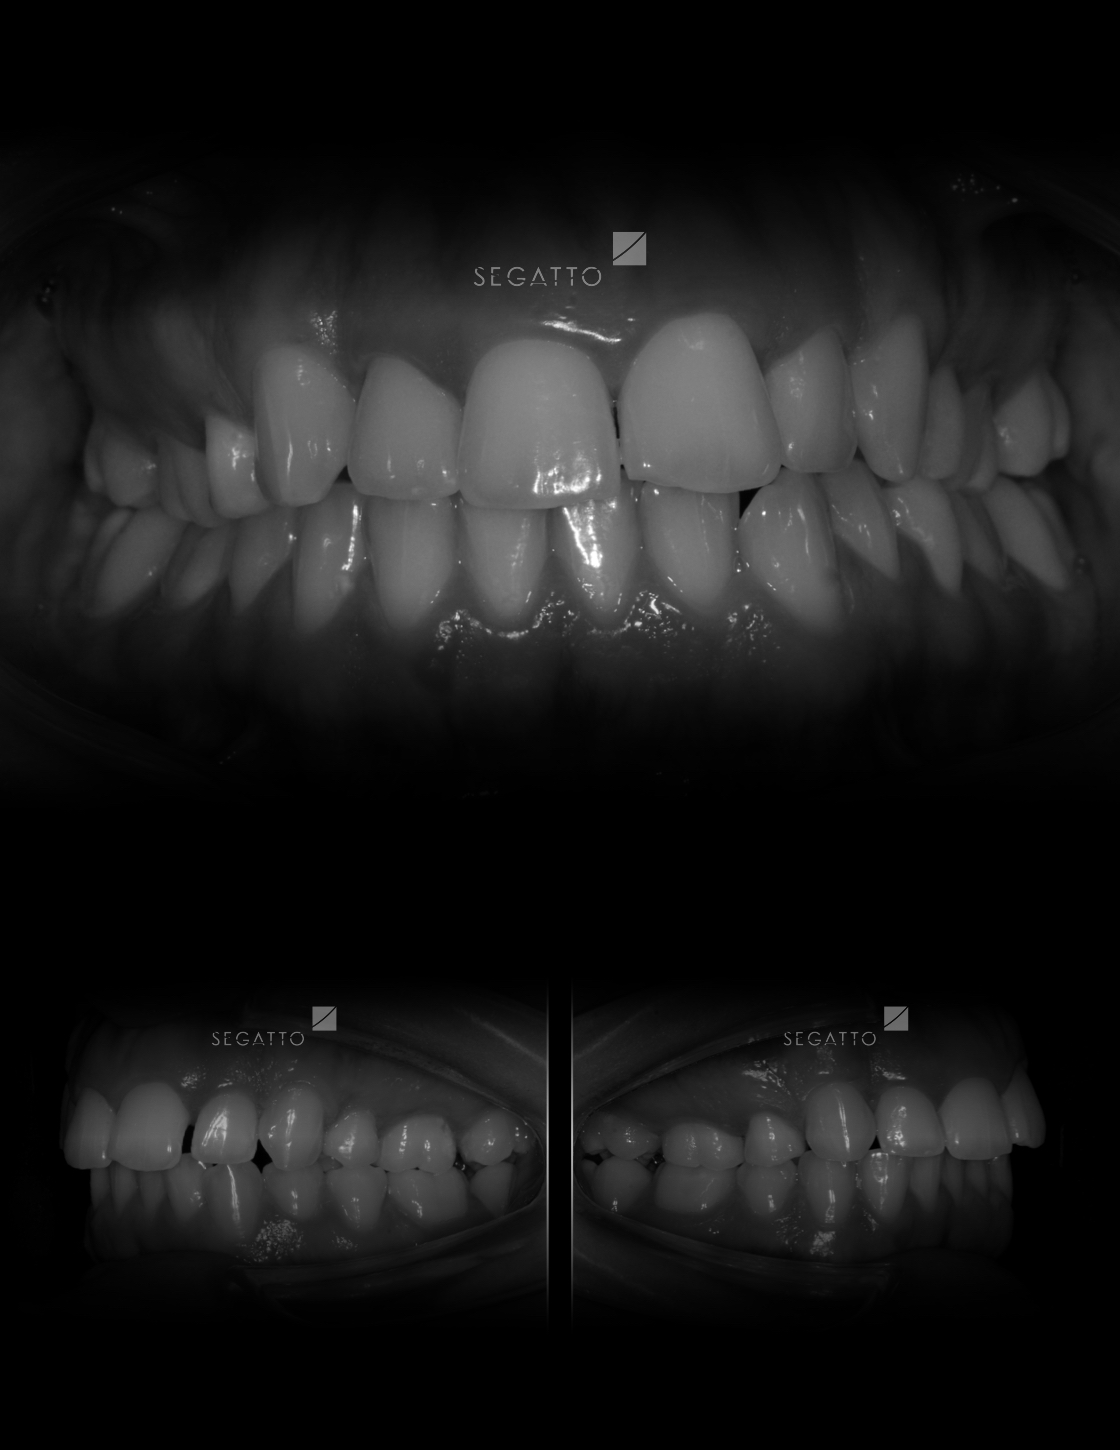

Orthodontics

Cases